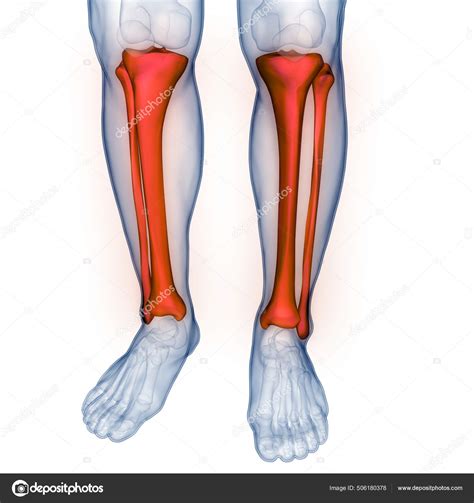

The tibia and fibula are the two long bones that make up the lower leg. The tibia, also known as the shinbone, is the larger and stronger of the two. It bears most of the body's weight and is crucial for standing and walking. The fibula, on the other hand, is thinner and runs parallel to the tibia on the outer side of the leg. It provides stability and serves as an attachment point for muscles and ligaments.

Structure of the Tibia

The tibia has several distinct parts:

• Proximal End: This includes the medial condyle, lateral condyle, and the tibial tuberosity, which is the site of attachment for the patellar tendon.

• Shaft: The long, cylindrical portion of the bone that provides structural support.

• Distal End: This includes the medial malleolus, which forms the inner ankle bone, and the lateral malleolus, which is part of the fibula.

Structure of the Fibula

The fibula also has key structural components:

• Proximal End: This includes the head of the fibula, which articulates with the tibia.

• Shaft: The long, slender portion of the bone.

• Distal End: This includes the lateral malleolus, which forms the outer ankle bone.